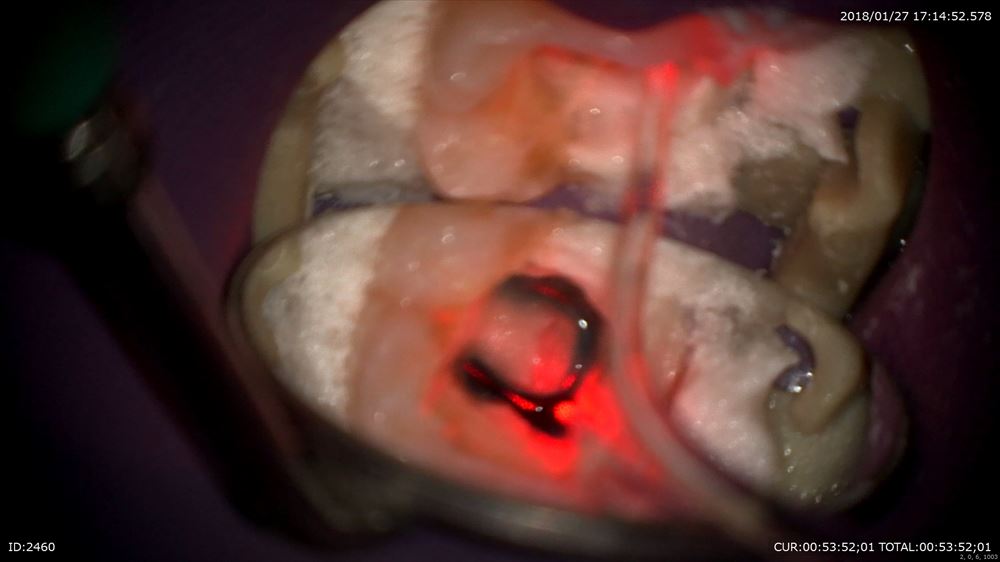

根管形成とレーザーで

ここまで1回で綺麗になりました。1時間半の治療時間です。患者さまに感謝!!